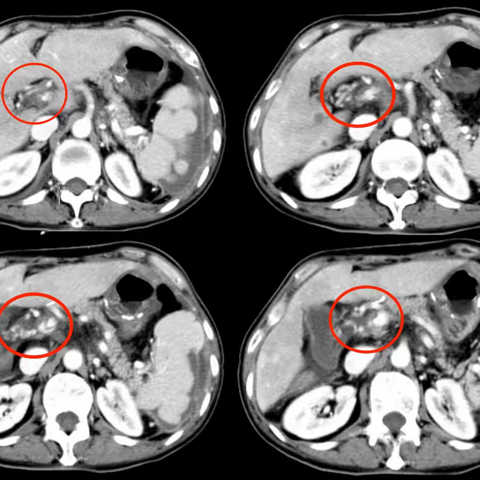

肝转移≠绝望重点!HAIC技术为晚期结肠癌患者打开生命“新窗口”

06-26 204阅读